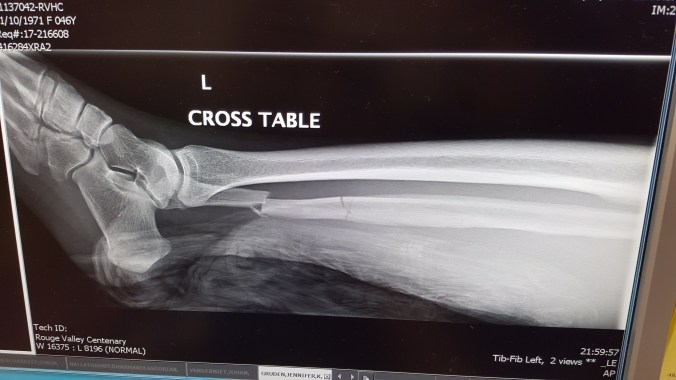

However in great irony, I broke my leg about two weeks ago!

The second time was two weeks ago. I was learning jumping side kick, which looks like this although…lower, less spectacular. One of my fellow students, who is a young man, was inspiring me and so as I took my steps towards the target I was picturing the way he had done it. It was a perfectly decent kick from all accounts, but the landing was a little rough. I heard a snap, went down, and sure enough, I broke my fibula in two places and have new hardware.